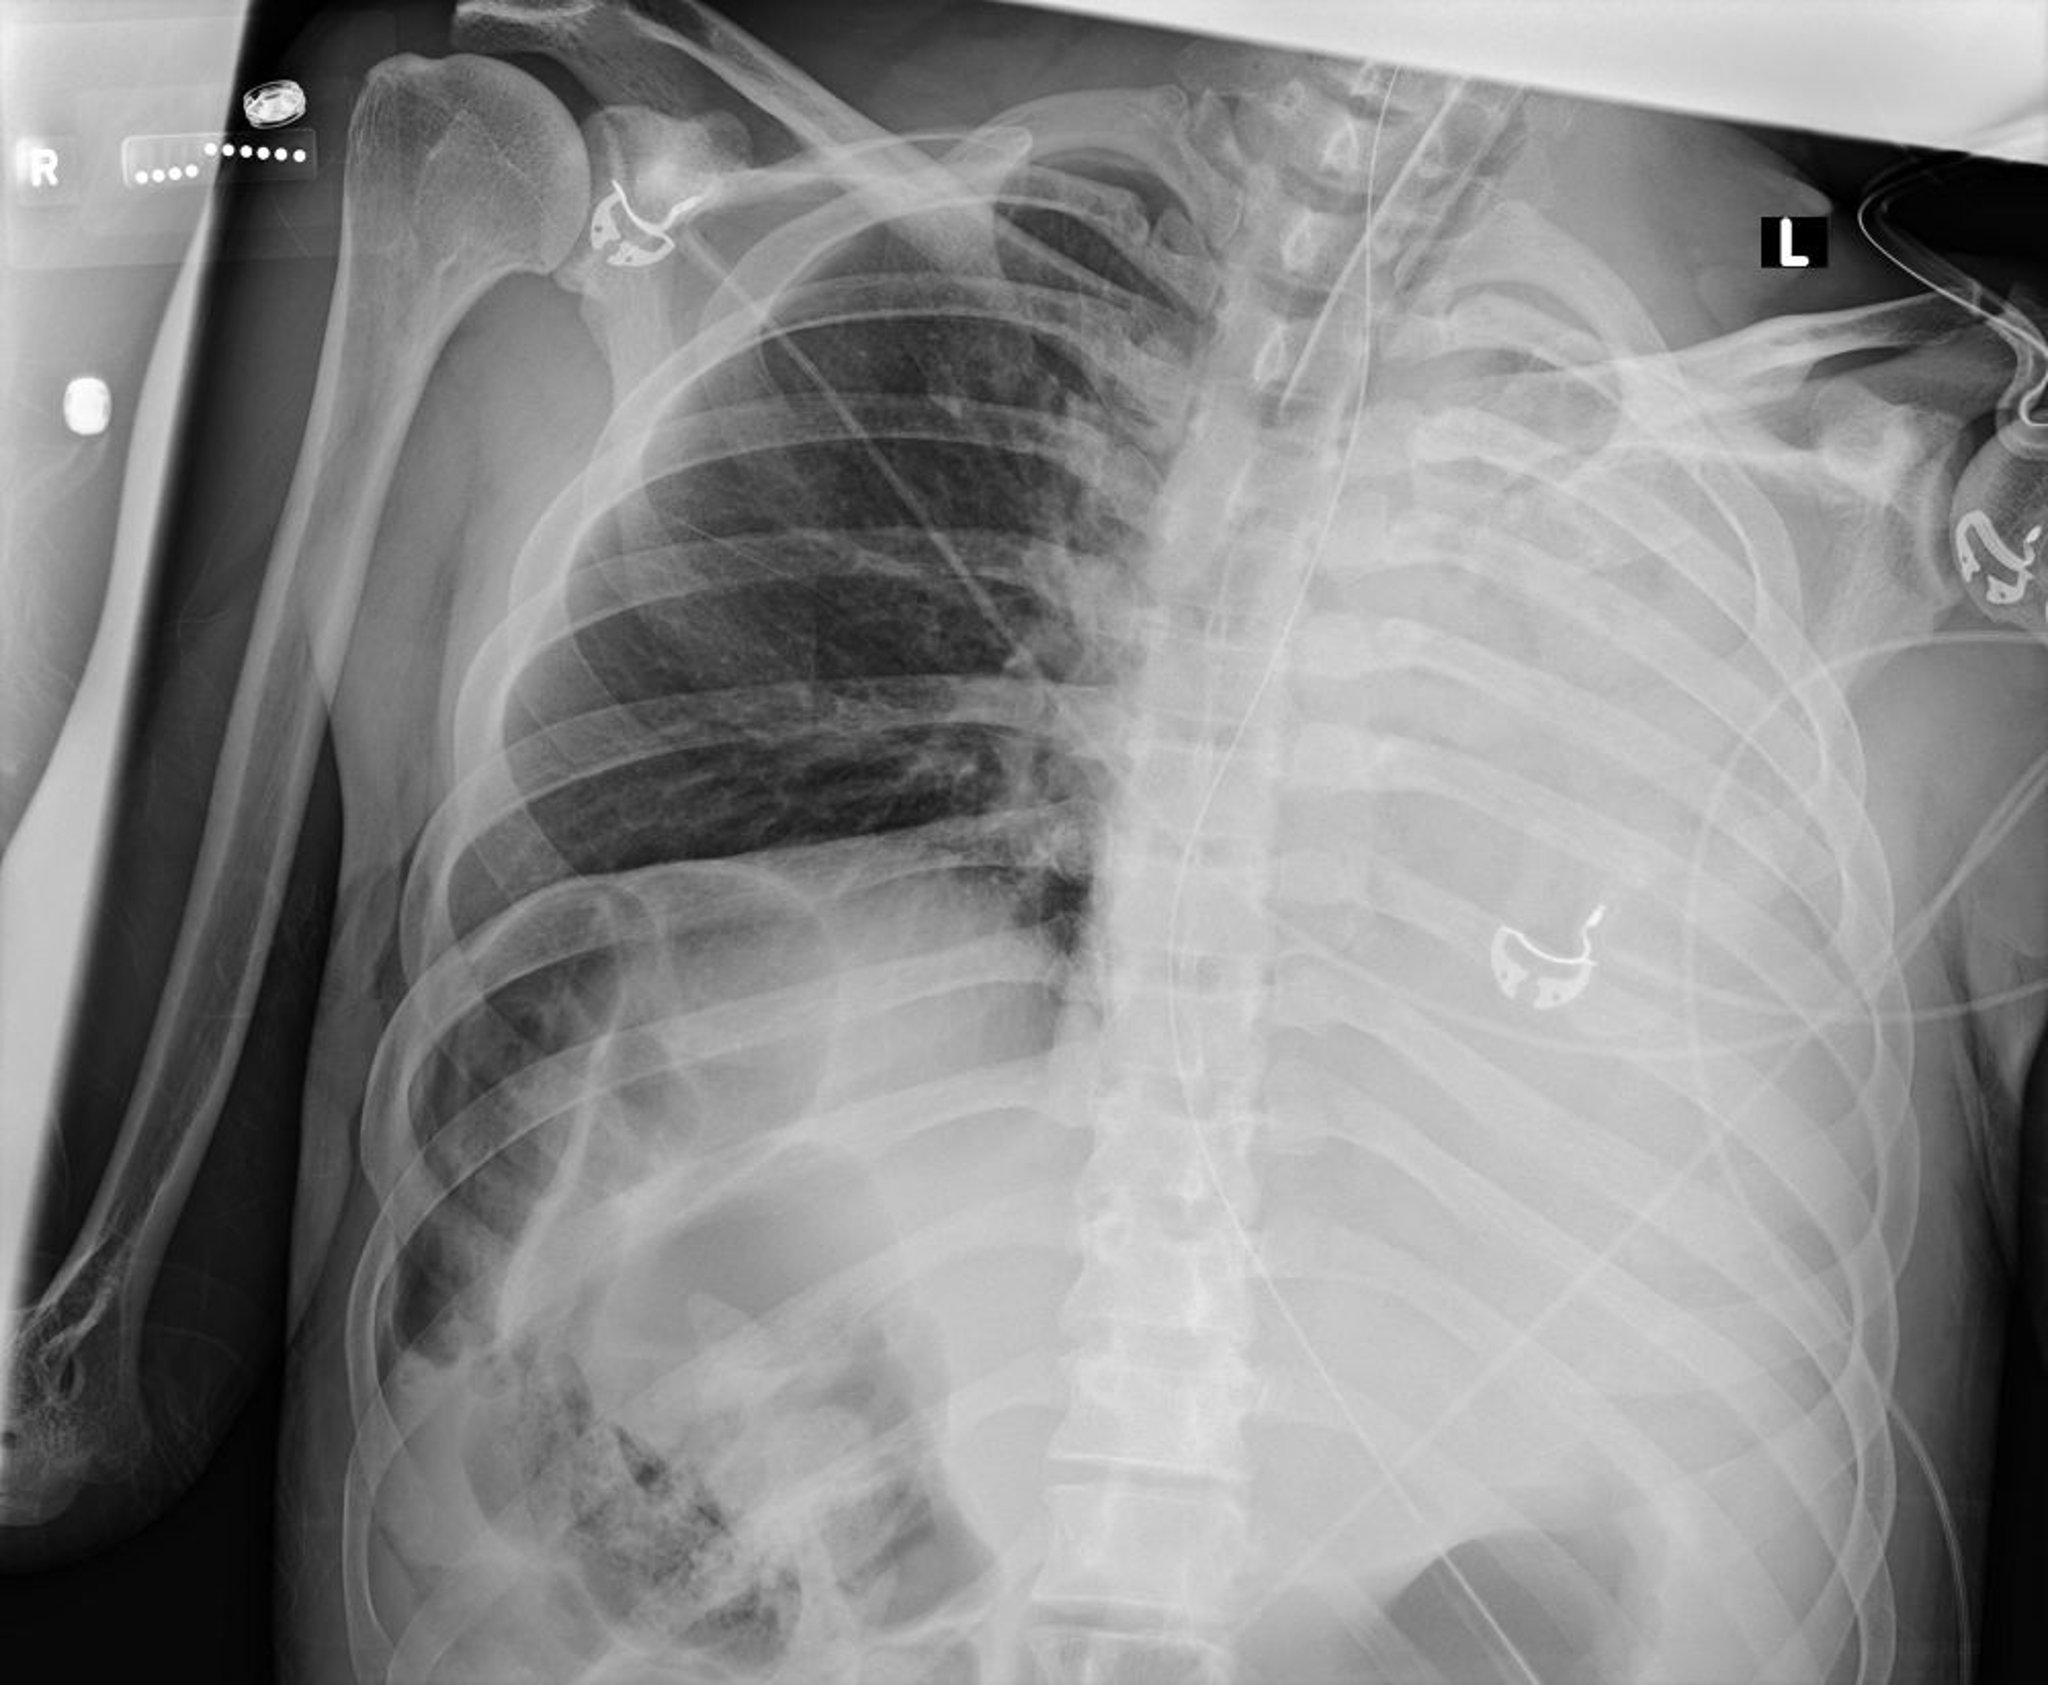

Deve-se suspeitar de atelectasia em pacientes que têm quaisquer sintomas respiratórios inexplicáveis e que têm fatores de risco, particularmente uma cirurgia de grande porte recente. A atelectasia que é clinicamente significativa (p. ex., que provoca sintomas, aumenta o risco de complicações ou afeta significativamente a função pulmonar) geralmente é visível na radiografia do tórax; os achados podem incluir opacificação pulmonar localizada e/ou perda do volume pulmonar. Casos mais leves podem não ser aparentes em radiografias de tórax e só podem ser vistos com exames de imagem seccionais (isto é, TC de tórax).

Esta radiografia do tórax mostra colapso de todos os lobos do pulmão esquerdo devido a um tampão de muco.

Courtesy of Alexander S. Niven, MD